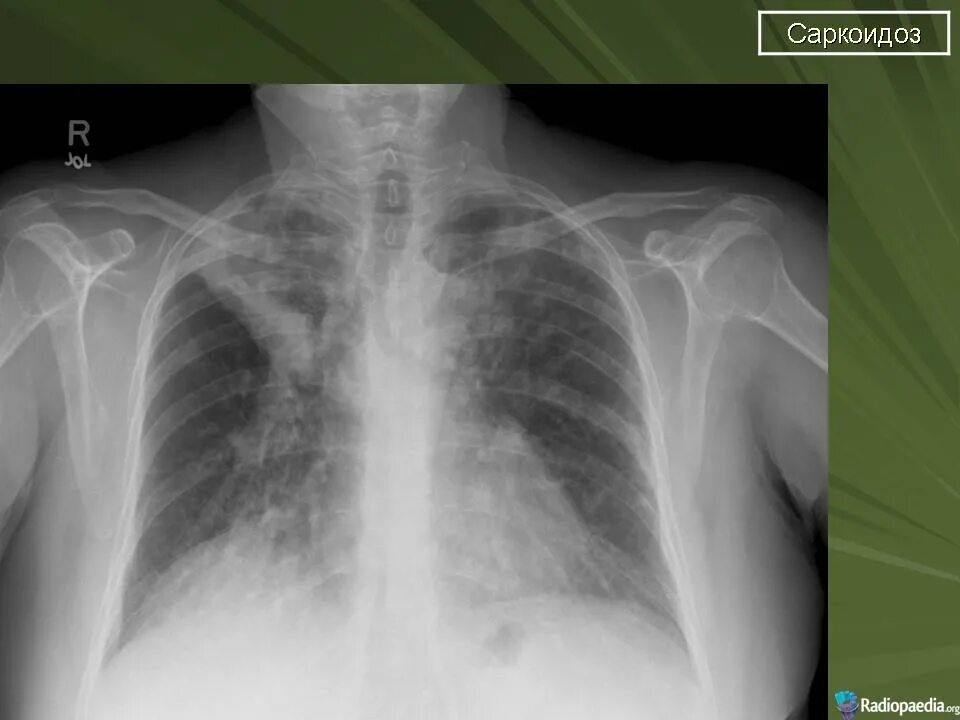

Саркоидоз 1